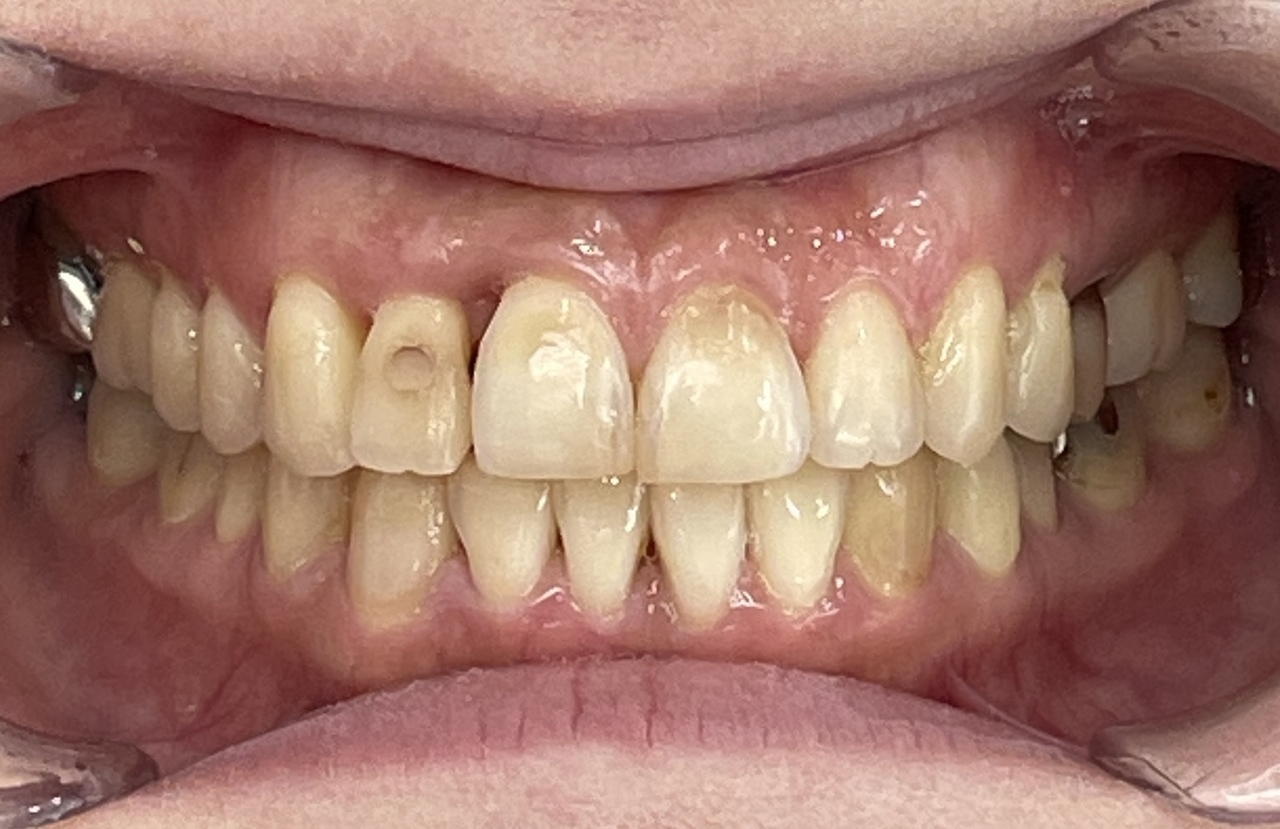

Before

After

矯正の種類 / invisalign GO

年齢・性別 / 30代男性

主訴  /  下の歯の叢生、オーバージェット、交叉咬合

治療期間 / 12ヶ月

費用 / 簡易検査 5,000円(税別) 精密検査 30,000円(税別)

両額マウスピース 450,000円(税別) 両額リテイナー料 40,000円(税別)

※マウスピース交換時別途調節料5,000円(税別)

副作用 / 口内炎・歯の移動に伴う痛み・知覚過敏 ※数日で収まる場合が多いです

リスク / 後戻り防止の為、夜のみマウスピースで保定を指示